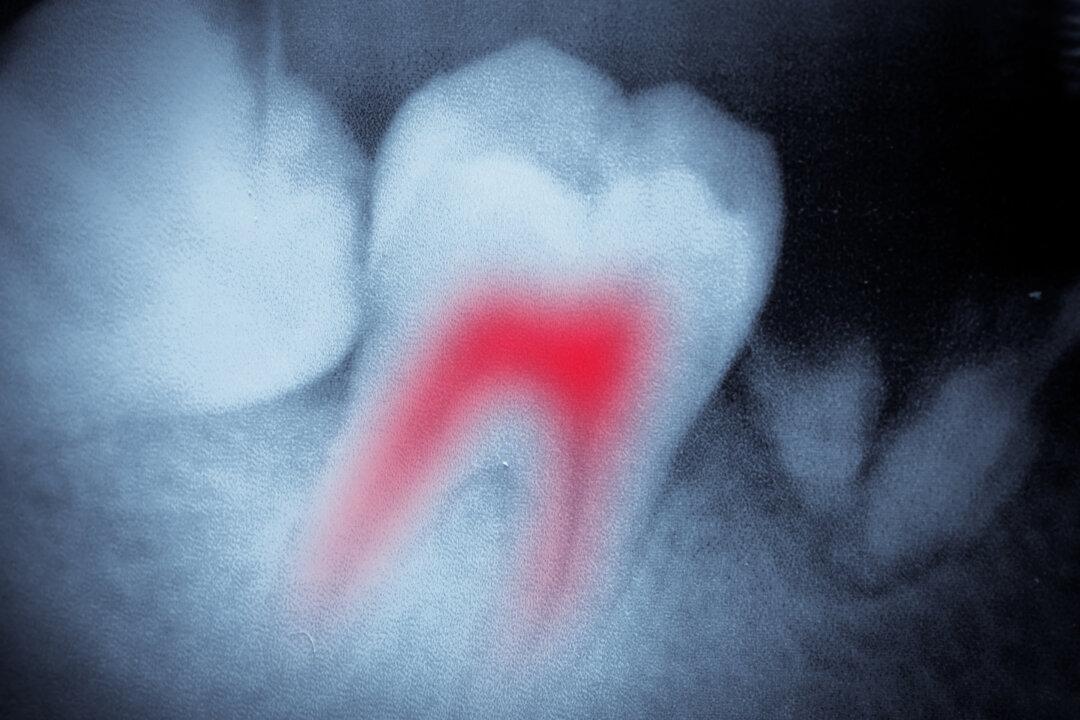

Can a root canal procedure increase the risk of disease? The evidence is clear – allow me to explain.

In our book The Toxic Tooth, Dr. Thomas E. Levy and I make the case that root canal-treated teeth remain infected, are a focal source of pathogenic bacteria and toxins that disseminate throughout the body, and are a cause of – or contributor to – a host of systemic diseases.